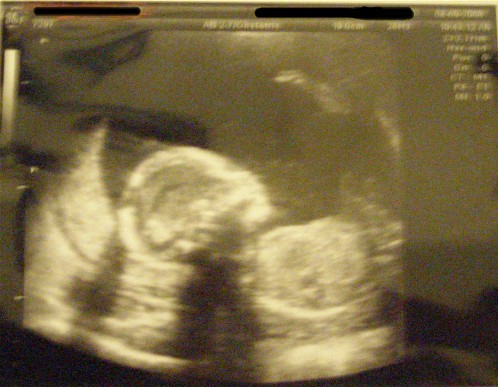

The Level 2 went well. Ed-lie Bubbles is measuring right on target. She is very healthy and moving around - tumbling and kicking - so much so that I may give her the last name "Tynes" in honor of the Giants' kicker who got them into the Superbowl. Here she is again:

Pretty bedding and great sono shots!!! There is no denying there is a girl inside your belly

what an Ed-lie filled day! The sono pictures are so great... I can't wait until our level II....